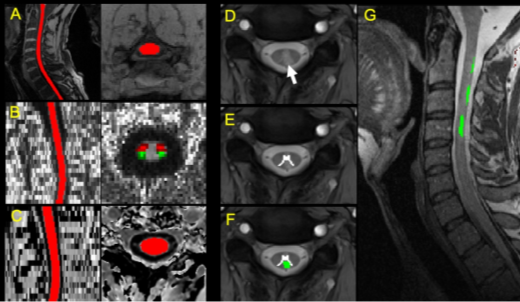

11月18日,中国科学院心理研究所行为科学重点实验室研究员孔亚卓和牛津大学临床神经科学系教授Jacqueline Palace团队在Brain上,在线发表题为Quantitative Spinal Cord MRI in MOG-Antibody Disease,Neuromyelitis Optica and Multiple Sclerosis的研究论文。该研究为单中心临床磁共振成像研究,运用多模态定量脊髓磁共振成像(quantitative spinal cord MRI)技术,招募多发性硬化症患者、MOG-Ab疾病患者、AQP4-Ab疾病患者和健康志愿者共80人,获取其颈部等区域脊髓的截面积、病灶分布、纤维束各向异性分数和磁转化率等定量指标(图1),用于区分三种中枢神经系统脱髓鞘疾病,并评估其与残疾指数和病理性疼痛等临床指标的关联性。

图1.(A)脊髓结构分割示意(B)各向异性分数(FA)图、脊髓丘脑束(红色)和皮层脊髓束(绿色)(C)磁转化图像分割(D)T2* 轴位图,显示灰质和病灶(E)灰质分割(F)病灶分割(G)病灶配准到T2结构像